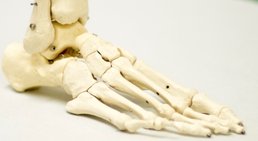

Als Mitglied der Österreichischen sowie der Deutschen Gesellschaft für Fußchirurgie umfasst mein Spezialgebiet die Behandlung sämtlicher Erkrankungen des Fußes.

Bei Hallux, Plattfuß und allen anderen Arten von Fußerkrankungen kann ich daher die modernsten konservativen Behandlungen sowie die aktuellsten Operationstechniken anbieten.

In meiner klinischen Tätigkeit als Oberarzt an der Abteilung für Orthopädie und orthopädische Chirurgie der Universitätsklinik leitete ich zuletzt die Spezialambulanz für Fuß- und Sprunggelenkserkrankungen und konnte zusätzlich meine zweite Facharztausbildung zum Facharzt für Orthopädie und Traumatologie abschließen.